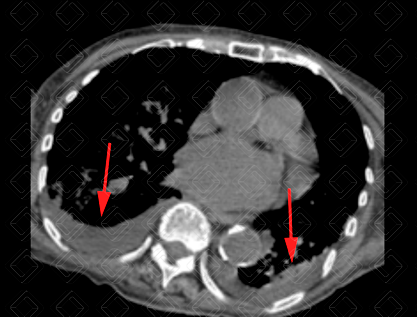

Descrição das figuras 1, 2 e 3: Adolescente de 16 anos, com desconforto respiratório e febre. Imagem A (figura 1): radiografia de tórax evidencia moderado derrame pleural (asterisco). Imagem B (figuras 2 e 3): exame foi complementado com tomografia de tórax com contraste, pela não melhora clínica. Observa-se o derrame pleural (seta vermelha) à direita e os nódulos centrolobulares (seta amarela) com padrão de árvore em brotamento à esquerda, achados muito sugestivos de tuberculose pulmonar, confirmada posteriormente.

• Tomografia computadorizada (TC) do tórax : Em geral, é usado somente nos casos mais graves, como suspeitas de neoplasia, complicação de derrame parapneumônico ou quando a causa do derrame pleural permanece desconhecida. Em geral, a densidade do derrame pleural na TC encontra-se entre 10-20 UH (densidade líquida). Figuras 1 e 2;